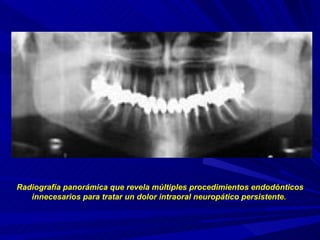

Radiografía panorámica que revela múltiples procedimientos endodónticos innecesarios para tratar un dolor intraoral neuropático persistente.

Radiografía panorámica querevela múltiples procedimientos endodónticos innecesarios para tratar un dolor intraoral neuropático persistente.